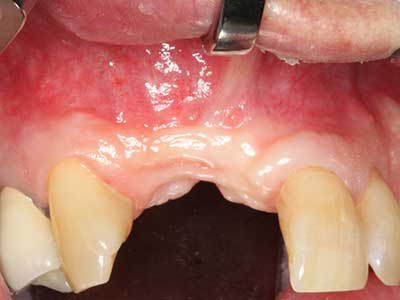

Indication: Periodontal therapy

Marginal periodontal diseases are the main reason for extractions in advanced age. These diseases are primarily caused by bacterial colonization of the gingival pocket, which causes inflammation followed by loss of the periodontium. The formation of subgingival biofilms and concrements is a significant aetiological factor for marginal bone atrophy, so their removal is an important part of the treatment (Drisko 2014, Plessas 2014).

Initial and surgical treatment phases are differentiated in the treatment of marginal periodontitis. In addition to instruction in oral hygiene and motivating patients, both phases should include adequate cleaning of the root surface. In the regenerative setting an open access is generally preferred. The root surface can be cleaned by piezosurgery using special attachments, where instruments with different curvatures are used to reach areas that are difficult to access, such as furcations. The integrated irrigation in the system flushes the detached concrements and bacteria out of the pocket. Specialized systems such as the Piezomed also include application feedback to minimize the ablation of hard dental substance. The greater the pressure on the periodontal attachment the greater the reduction in the amount of ablation.